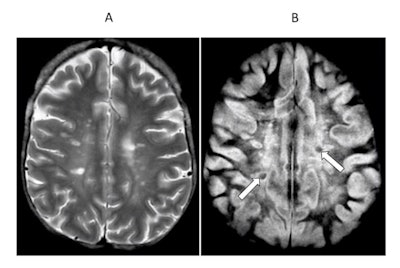

Transverse image of the brain in a case of multiple sclerosis T2 spin-echo (SE) (A) and subtracted inversion recovery (SIR) (B) images. Very long T1 high signal lesions are seen in (A) and show intermediate signal in (B) (arrows). Other lesions appear much more extensive in (B) where abnormalities extend towards the peripheral U fibers in most of the white matter.  Image courtesy of Ya-Jun Ma, Hongda Shao, et al and Quantitative Imaging in Medicine and Surgery.

Transverse image of the brain in a case of multiple sclerosis T2 spin-echo (SE) (A) and subtracted inversion recovery (SIR) (B) images. Very long T1 high signal lesions are seen in (A) and show intermediate signal in (B) (arrows). Other lesions appear much more extensive in (B) where abnormalities extend towards the peripheral U fibers in most of the white matter.  Image courtesy of Ya-Jun Ma, Hongda Shao, et al and Quantitative Imaging in Medicine and Surgery.For instance, the effect of this subtracted inversion recovery (SIR) sequence can be seen in a patient with multiple sclerosis (above) where focal lesions appear in the white matter with a T2-weighted spin-echo sequence, while much more extensive changes are seen throughout most of the brain with the SIR sequence.

"The increase in T1 produced by the lesions is used synergistically by each of the two parts of the SIR sequence to increase contrast," Bydder said.